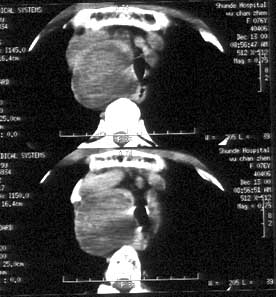

图:甲状腺结节伴点状钙化

甲状腺钙化是指甲状腺结节内出现的钙沉积的现象。甲状腺良性疾病出现钙化较少,通常是由于炎症、血肿吸收机化后形成的结节壁钙化或纤维隔带钙化。甲状腺肿瘤的钙化是由于癌细胞生长迅速,肿瘤血管及纤维组织增生,从而导致钙化。

实际上,点状钙化即微钙化表现为点状强回声,不论后方是否出现声影,可见于40%~61%的乳头状癌,但也可见于其他良性和恶性病变,如滤泡状癌、分化不良性癌、结节性甲状腺肿、滤泡状腺瘤和桥本氏甲状腺炎等。粗钙化多见于良性结节,尤其是结节性甲状腺肿。边缘钙化指位于甲状腺结节边缘部位的钙化,常见于结节性甲状腺肿,是良性结节的标志。